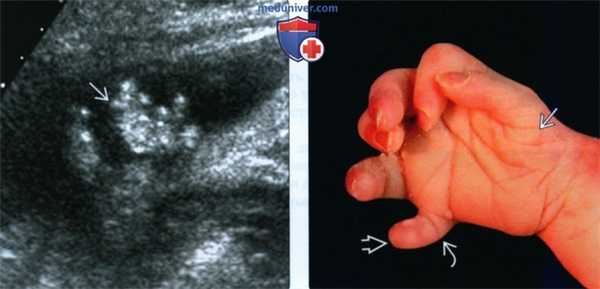

(Слева) УЗИ плода с тяжелой формой ССЛО в III триместре, сагиттальная плоскость. Определяются выраженный отек кожи, короткий вздернутый нос и микрогнатия. Также присутствует тяжелая форма микроцефалии.

(Справа) Клинические признаки ССЛО. Лицевая дизморфия (расщелина нёба и губы) и широкая переносица. Сложная синдактилия и инсерционная полидактилия.

(Слева) При УЗИ плода с ССЛО в III триместре определяется постаксиальная полидактилия. В ходе исследования выяснилось, что пальцы неподвижны.

(Справа) Кисть этого же новорожденного: гексадактилия и постаксиальная полидактилия. Обращает внимание положение пальца во время пренатального УЗИ. Отмечается гипоплазия мышц тенара, а также единственная сгибательная борозда шестого пальца.